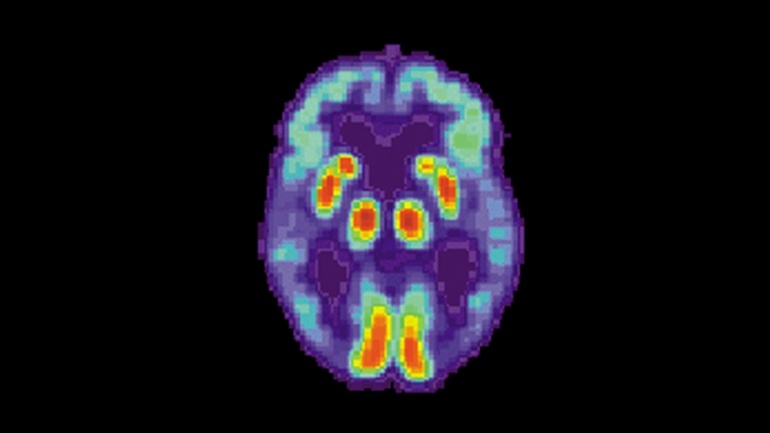

ПЭТ-скан мозга человека с тяжелой формой болезни Альцгеймера

Используя снимки обычного сканирования мозга, исследователи смогли научить алгоритм определять раннюю стадию развития болезни Альцгеймера – за 6 лет до того, как такое же заключение дает традиционный медицинский диагноз в клинике. Это может позволить нанести еще один удар по одной из самых страшных болезней (третьей основной причиной смерти в развитых странах после проблем с сердцем и рака).

Пока что лекарство для восстановления когнитивных способностей пациентов с деменцией отсутствует, можно разве что смягчать симптомы. Но буквально в последние месяцы начали появляться потенциальные способы бороться с развитием болезни. Читать полностью »